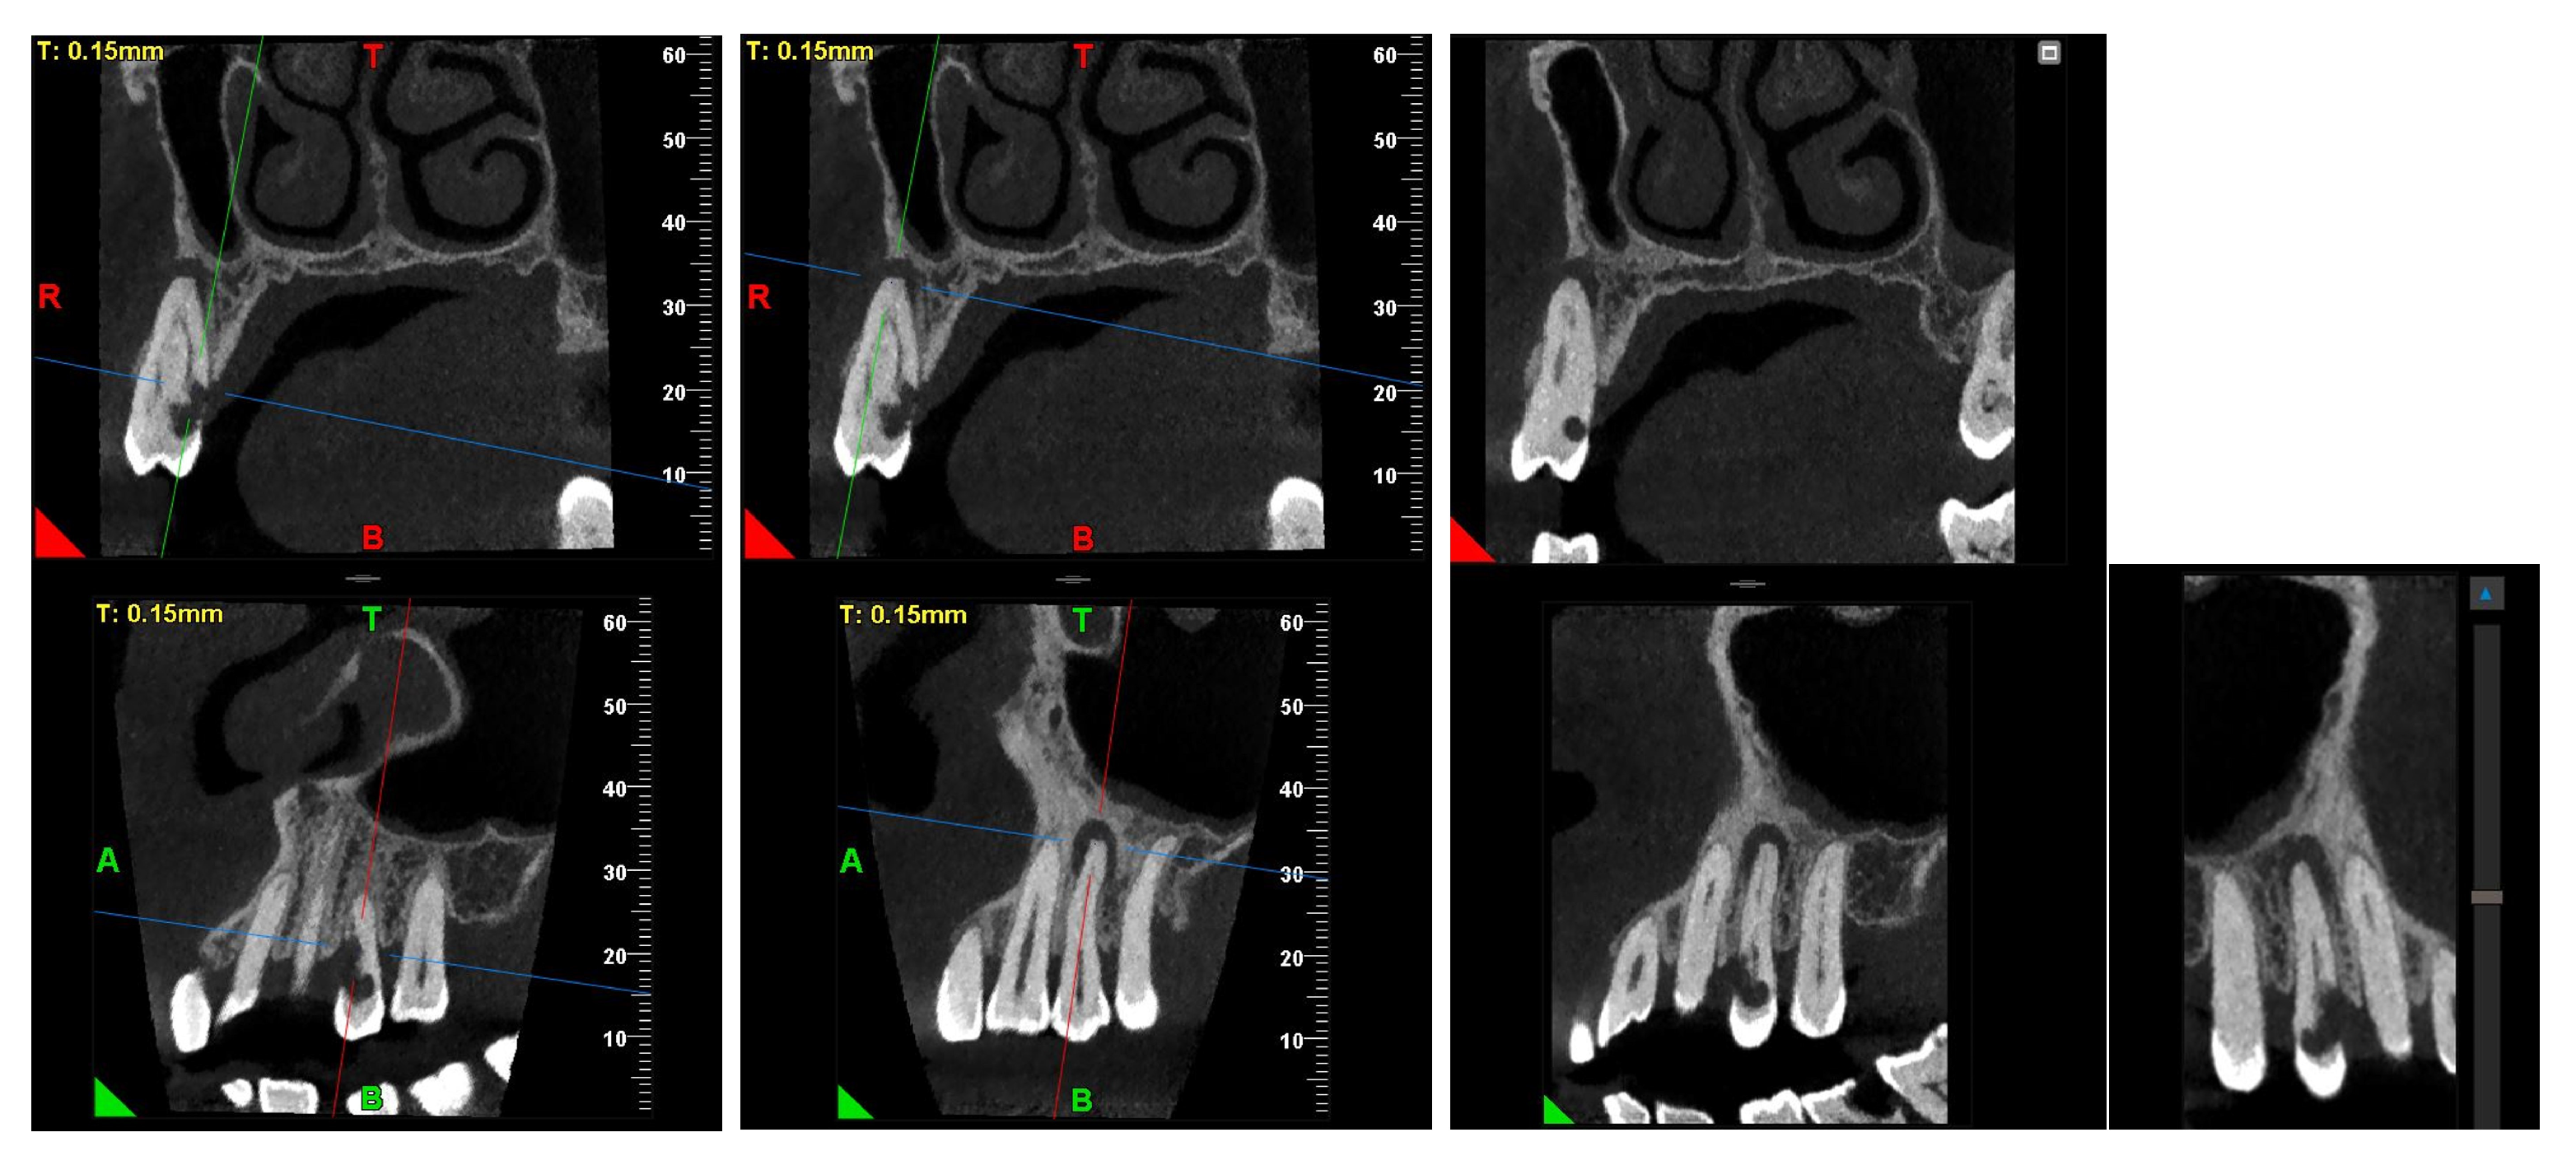

A CBCT examination (X9 Pro®, MyRay, Imola, Italy), performed with dedicated field of view (FOV) (6 × 6) and exposure parameters, was essential for accurate diagnosis and treatment planning. This device optionally features a specific Booster function for users with advanced expertise, which allows for further customization of exposure parameters to optimize the examination more effectively. Optimal management of the FOV, properly centered and limited to the anatomical area of interest, in this specific case slightly extended (6 × 6) to clearly rule out a possible involvement of the maxillary sinus in agreement with the attending otorhinolaryngologist, enabled the acquisition of broader and more detailed clinical and diagnostic information, which is essential in endodontics. Moreover, it allowed for a significant reduction in radiation dose while optimizing spatial resolution [22]. The imaging clarified the extent of the resorption and defined its perimeter, demonstrating an endodontic-periodontal communication, classified as 3Bp according to Patel’s classification [21] (Figure 2, Figure 3, Figure 4 and Figure 5).

Figure 2.

Axial CBCT images of tooth 1.4, showing its ECR and PL. (A–E) Sequential scrolling on the axial plane from the cervical area to the middle third of the root; (F,G) Segmentation of Figure 2E using the advanced software functions iRYS® (MyRay, Imola, Italy); (H,I) Sequential scrolling on the axial plane of the apical third of the root, including the PL.

Figure 3.

Cross-section and Pano-rex CBCT images of tooth 1.4 and its ECR and EPL. (A,B) Sequential sagittal scrolling allows the evaluation of the lesion in the bucco-lingual direction and its continuity along the root axis; (C,D) Segmentation of Figure 3B using the advanced software functions iRYS® (MyRay, Imola, Italy); (E) Interface of the aforementioned software to obtain segmentation on Pano-rex image. (F) Pano-rex image of tooth 1.4 and its EPL. (G,H) Segmentation of Figure 3F using the advanced software functions. The colored lines crossing the images represent the orthogonal planes (axial, coronal, and sagittal) in the multiplanar reconstruction. Their correct use and orientation allow for an accurate identification of the extent of the lesions in all spatial planes and a detailed analysis of the endodontic anatomy. The green letters are the coordinates of the image: A: anterior, B: bottom, T: Top.

Figure 4.

Pano-rex and cross-sectional CBCT images of tooth 1.4, showing its ECR, EPL, and PL. The colored lines crossing the images represent the orthogonal planes (axial, coronal, and sagittal) in the multiplanar reconstruction. Their correct use and orientation allow for an accurate identification of the extent of the lesions, including possible relationships with the maxillary sinus, in all spatial planes and a detailed analysis of the endodontic anatomy. The green and red letters are the coordinates of the image: A: anterior, R: right, B: bottom, T: Top.